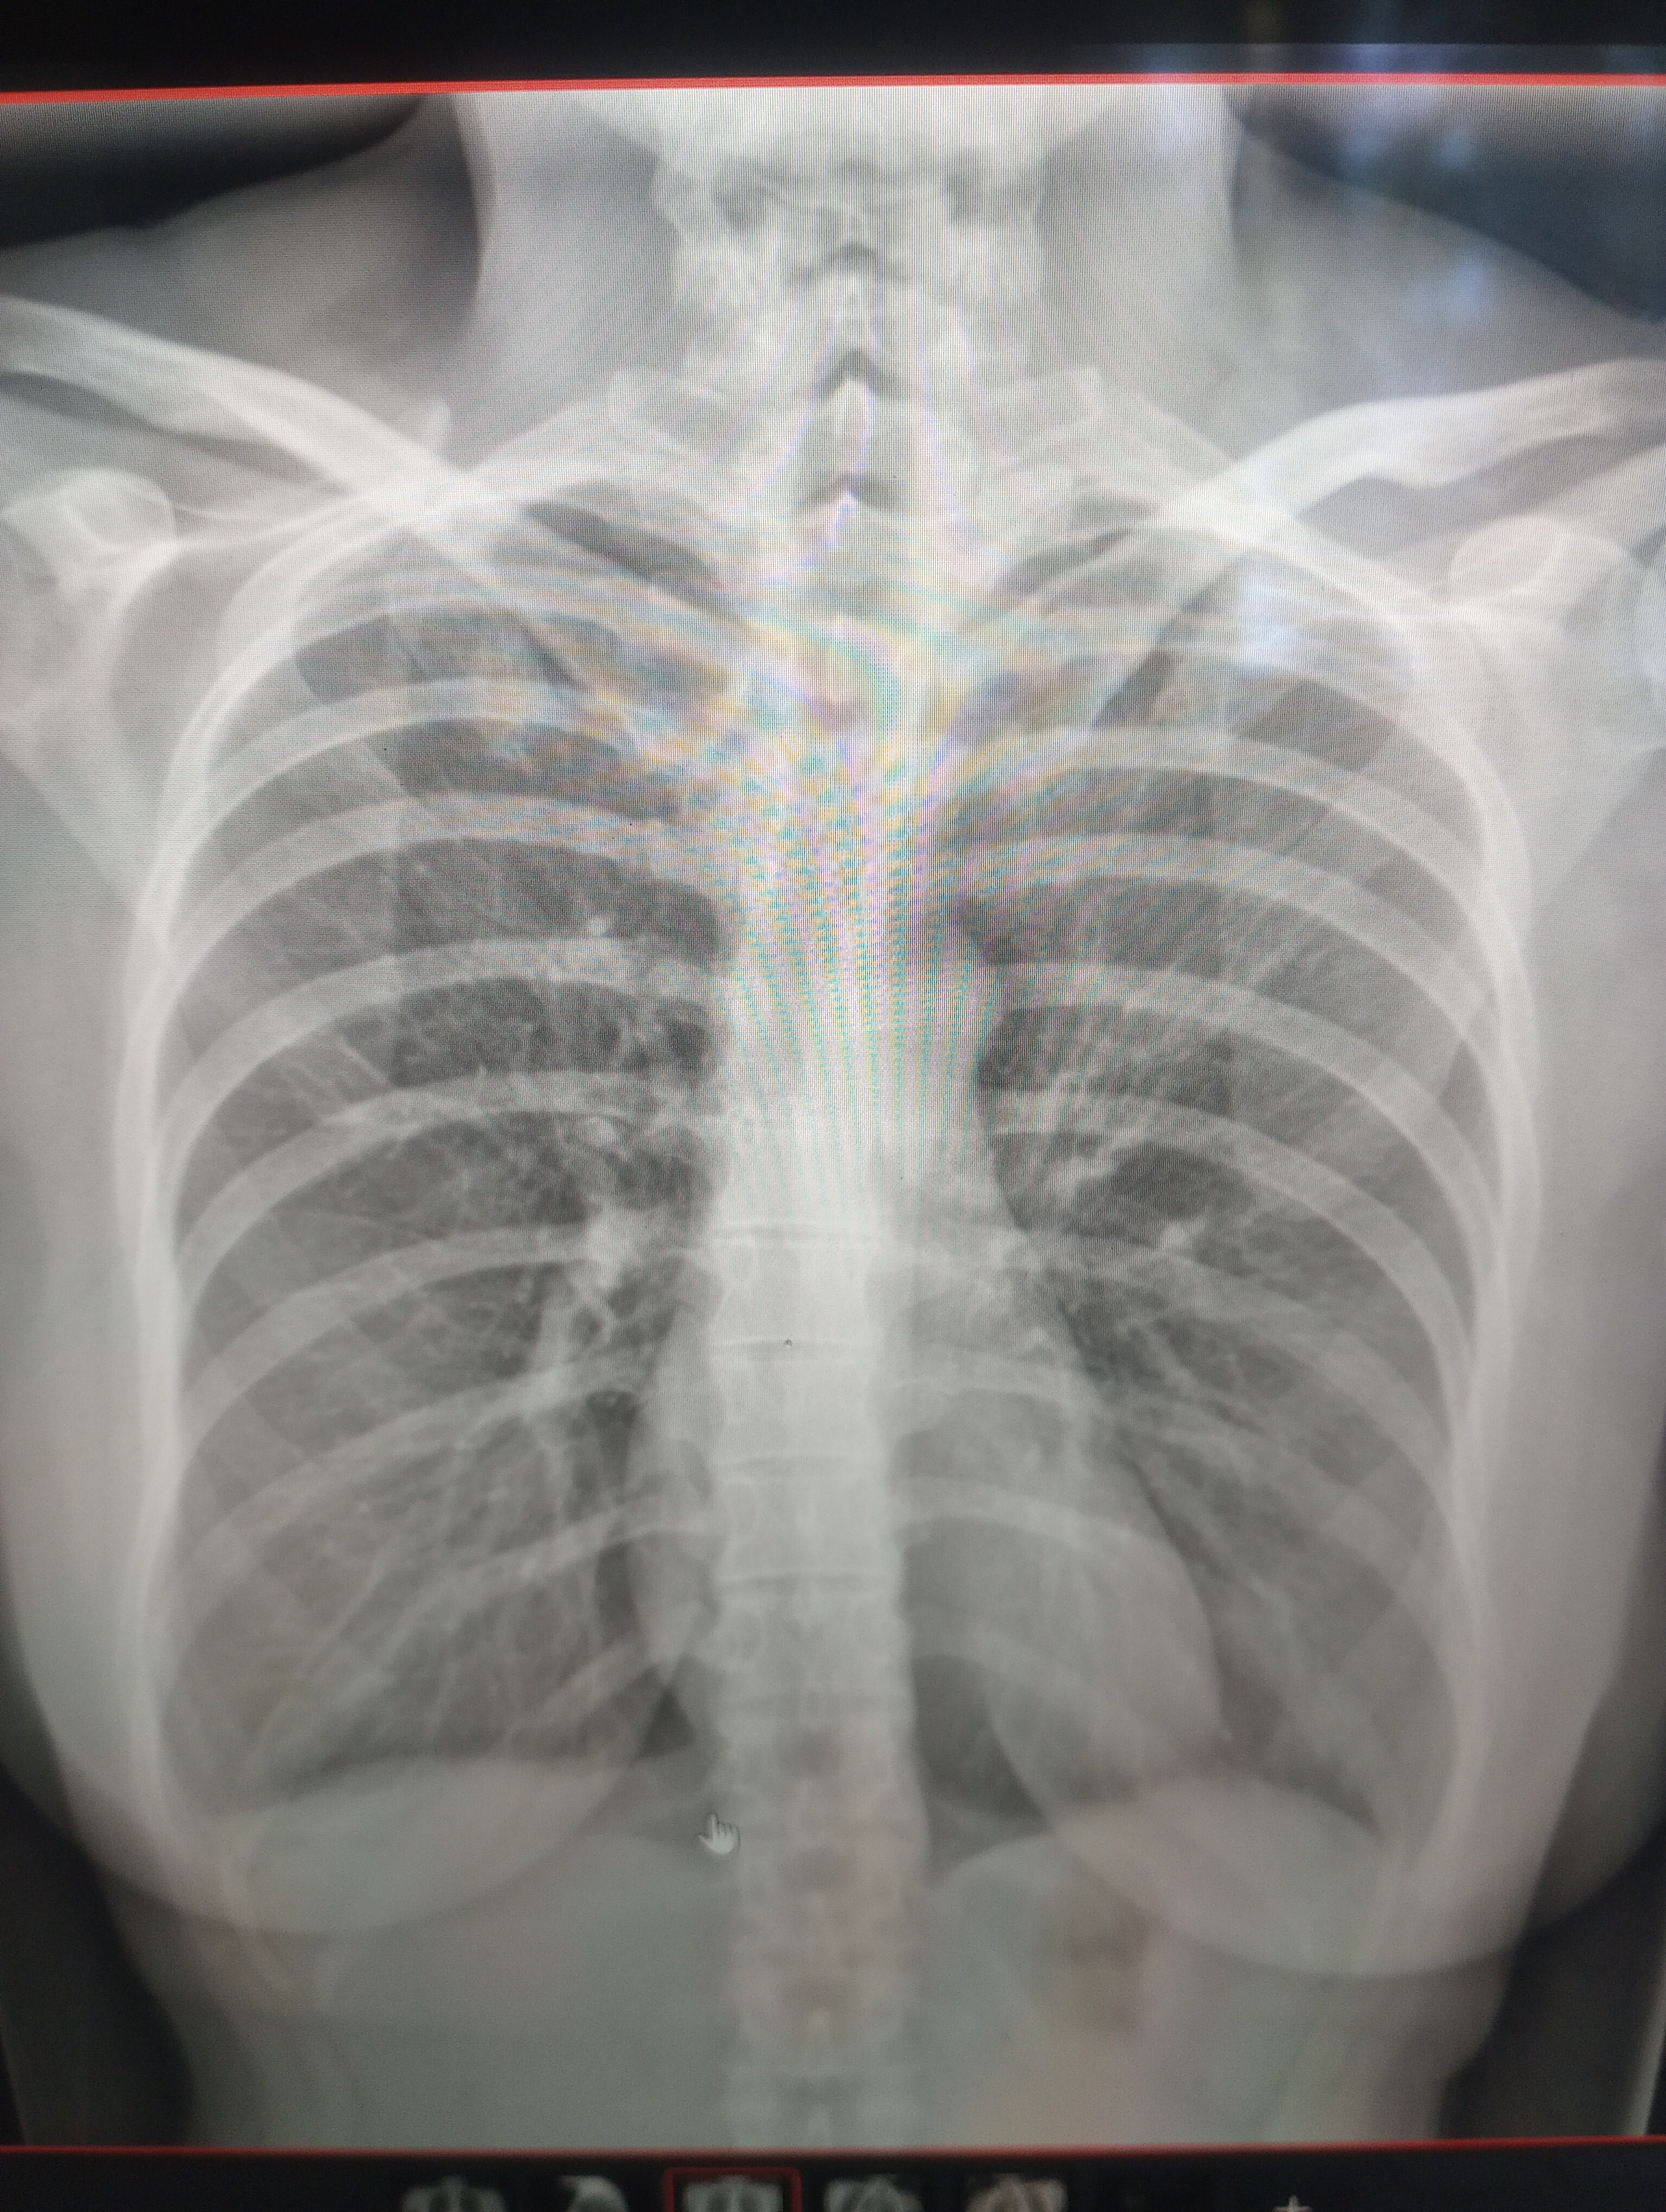

Hello friends, I'm a single mom whom has always made ends meet until now. A long time ago I had a very invasive surgery which I was promised a quick recovery from which took myself by surprise because I never felt okay after. I had a breast augmentation done to my chest under the muscle. I learnt very quickly that, that meant a lot of residual pain. This was lived with until I started swelling to the point that I fractured 6 ribs bilaterally. Then after extreme pain I healed and then broke 4 more ribs on my right side. All though my healed my ribs broke and rebroke until they were healed leaving me with great nerve pain which traveled around my waist, down my arms and then to my face. Causing even my tongue to turn white. I've tried very hard but I can still not sit up for very long. I feel pulled into laying flat. This affected my ability to walk forcing me to use a walker everywhere I went. At the same time as dealing with all of this I was making meals and prepping the house for my daughter. I was forced to scan one bone at a time so I was constantly having to commun to the hospital by myself in great pain. I did not have enough money this entire time to make ends meet which really put another layer of stress. My pain was a ten but now that it is slightly controled I would like the pressure of the implants off my chest to save my arms which are currently dislocated at the ulnar nereves. I really need help to make the next step in healing to get these implants removed because I know deep down they are the reason my ribs broke. This story is what nightmares are made out of because one of the side effects of all this is it takes me away from my precious duties as a healthy mom. It breaks my heart that one surgery holds me back from so much. If I do manage somehow to raise the money it will go directly to the surgeon. I have given up on the surgeons in BC. They don't return calls or show any amount of care. Therefore I'm looking to Mexico for help.